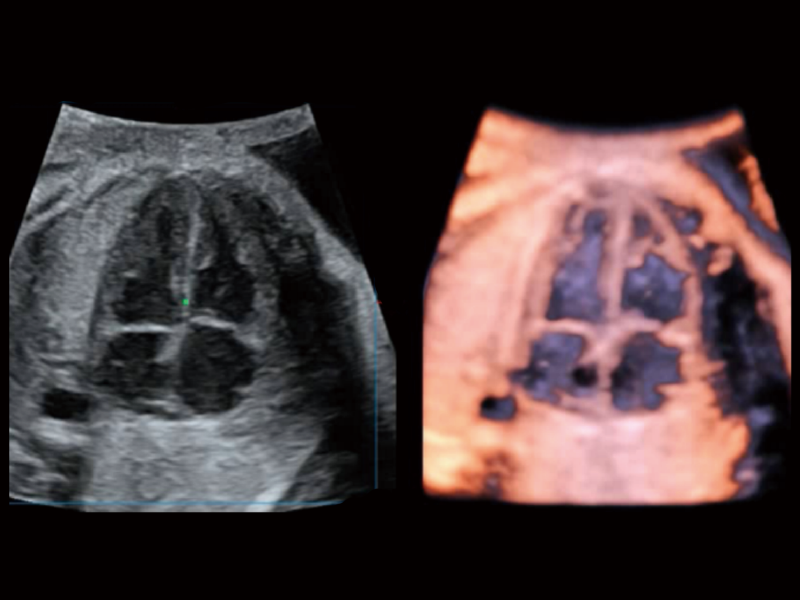

胎兒顱腦融合

時(shí)間空間相關(guān)成像